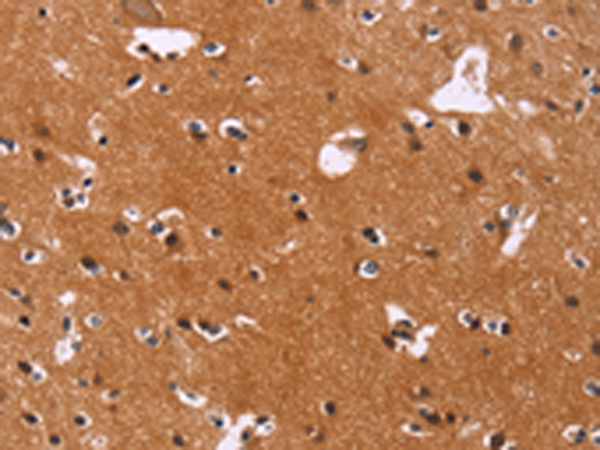

分类: 科研抗体货号: P03985别名: GDNFR; RET1L; RETL1; TRNR1; GDNFRA; GFR-ALPHA-1应用: WB,IHC反应种属: Human, Mouse, Rat